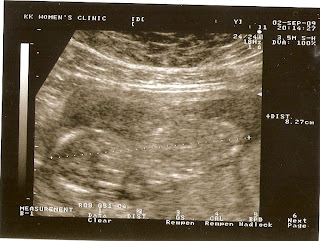

Our Little Angel 14 weeks

Seem like a long wait.... now is the 14 weeks of pregnant... still have long long way to go before i can hold Little Angel in Our Arm... Have an appointment with Doctor Anthony again.. but today is @ KKH clinic @ AMK.... the wait is not so long... at least don't have to travel so far.. hehe.. getting lazy... before the checkup i was so worry... cause don't know how Little Angel will look like... My Mum & Hubby tell me to relax.. & Don't think so much about it.. Don't stress myself too much....

As for the Second scan.... i can see Little Angel Head, Body, Little hand & Feet... but i was quite Surprise that i can see the nose & little mouth... Hee Hee.. was so happy after the scan... looking forward for the next scan.. when Little Angel is 21 weeks ( 12 Oct 2009, Mon ).. Doctor will do a detail scan.. & check is a Boy Boy Angel Or a Gal Gal Angel... Hubby apply leave to go with me... i think both of us is looking forward to that day.... Hopefully Little Angel will be Guai Guai let us see... hee....